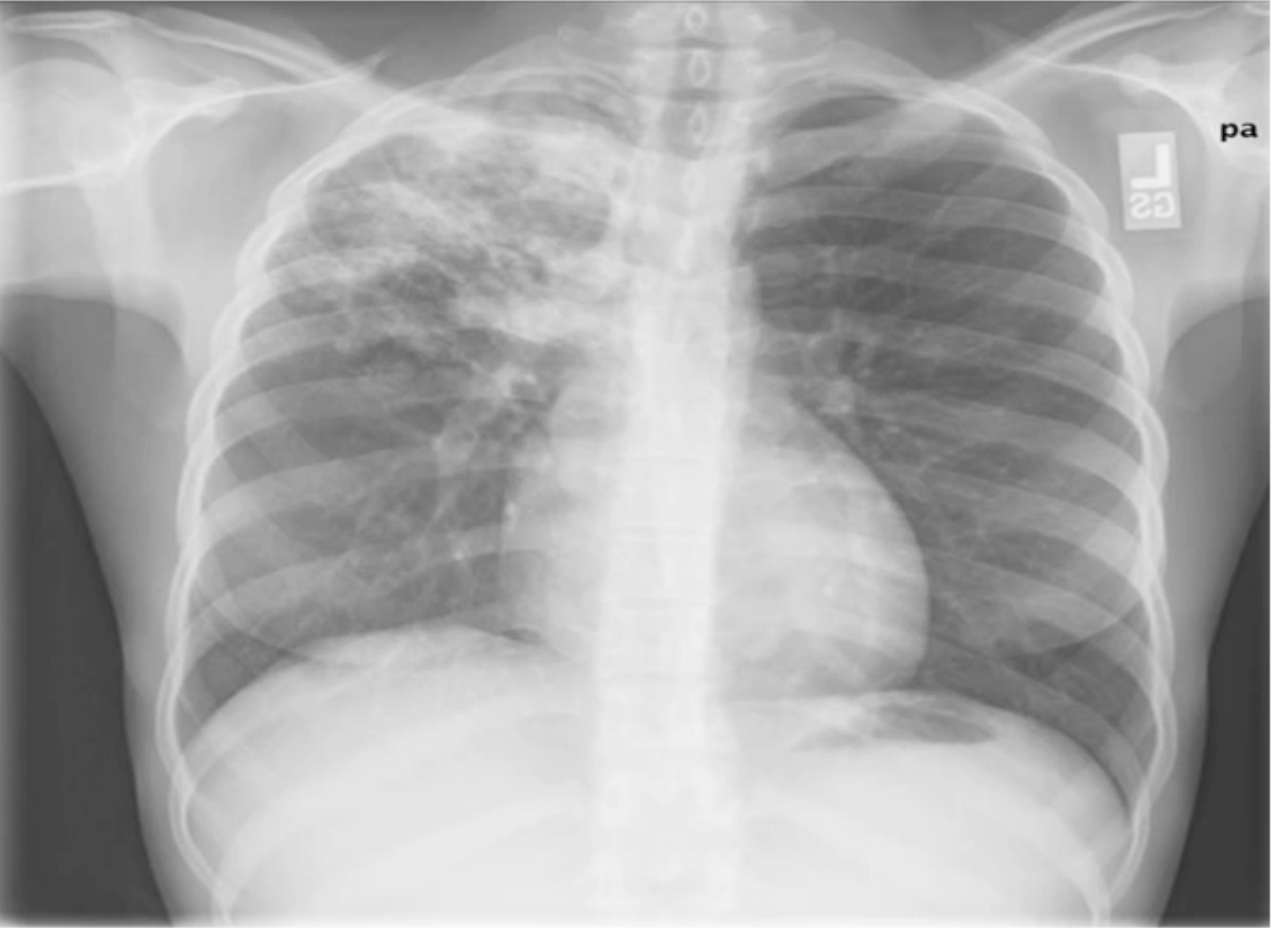

A Pneumothorax patient improved after chest drain insertion. However, they complain of recurrent SOB after 2 hours. What is the cause of the recurrent SOB indicated by the repeat CXR seen here?

Re-expansion Pulmonary Oedema as a complication of Chest Drain insertion.